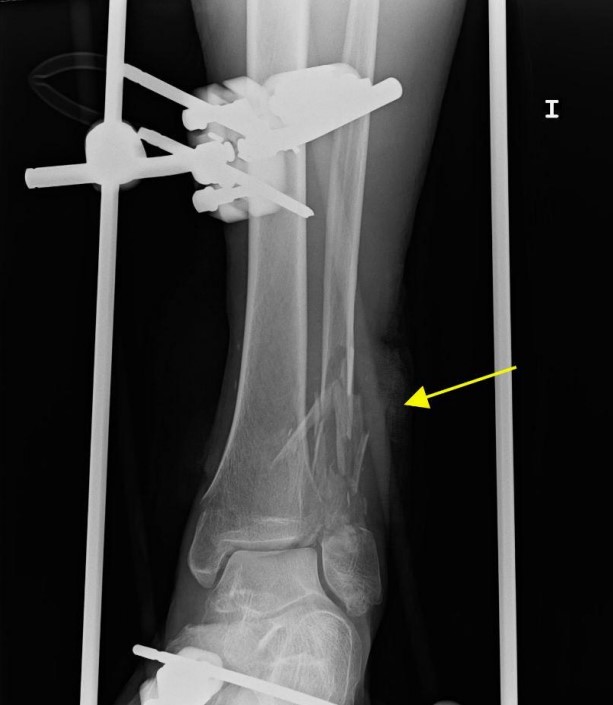

患者左下肢X線片顯示腓骨和脛骨骨折。胸片顯示上肺葉雙側(cè)肺泡混濁,這些不明確的斑片狀氣腔模糊是非特異性的,可見于肺水腫、誤吸或感染。繼續(xù)為患者行胸部CT檢查,CT顯示肺動(dòng)脈干、左或右肺動(dòng)脈主干或肺葉動(dòng)脈無充盈缺損,雙側(cè)胸腔積液。肺窗顯示雙側(cè)上、左中肺野斑片狀磨玻璃影伴小葉間隔增厚。

圖1 左下肢X片。外固定器處理腓骨和脛骨骨折移位(黃色箭頭)